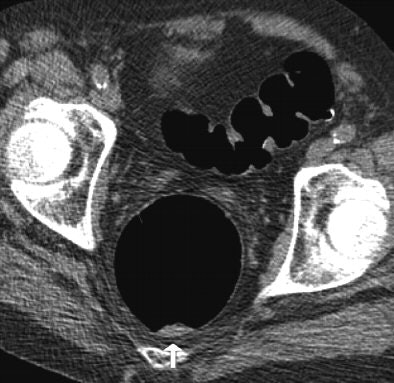

| Above: Supine image of rectum in a 64-year-old woman shows nontagged material 6 mm or greater with small hyperdense spot in dependent part of rectum (arrow). Hyperdense spot probably corresponds to some barium. Below: Prone view of rectum in the same patient shows nontagged fecal material has moved to anterior rectal wall (arrow). Image shows nontagged feces 6 mm or larger in rectum, possibly caused by remnants of bisacodyl suppository. P Lefere, S Gryspeerdt, J Marrannes, M Baekelandt, B Van Holsbeeck, "CT Colonography After Fecal Tagging with a Reduced Cathartic Cleansing and a Reduced Volume of Barium" (AJR 2005, 184: 1836-1842). |

Overall the researchers found residual feces in 413 segments (34.41%), including fecal material smaller than 6 mm in 210 segments (17.5%) and 6 mm or larger in 203 segments (16.92%). In addition, 527 segments contained residual fluid (43.91%), detected as it moved between prone and supine imaging. Nontagged feces 6 mm or greater were present in 49 segments (4.08%) and nontagged fluid in 178 segments (14.83%).

"The false positives were caused in four patients because of diverticulosis with severe luminal narrowing and thickening of the folds," Lefere and colleagues commented. In these cases, a differential diagnosis that included carcinoma was made. Only 4% of segments presented with untagged feces 6 mm or larger, and this result was limited to the presence of one fecal ball in more than two-thirds of these patients.

"The good results of tagging are reflected in the results of polyp detection," Lefere and colleagues wrote. "In fact, there were no false-positive findings caused by nontagged feces. Three false negatives of a total of 68 lesions 6 mm or greater were reported. Only one lesion of 6 mm or greater was overlooked, and it was detected retrospectively. The two other lesions were adjacent to another lesion and were hence misinterpreted as being a bilobulate rather as being two separate lesions."